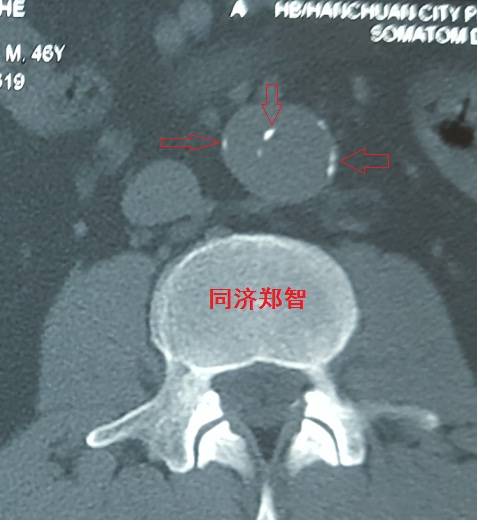

病例四

腹部平扫CT提示腹主动脉增宽,CTA证实为腹主动脉局限性夹层(红箭头所示)。